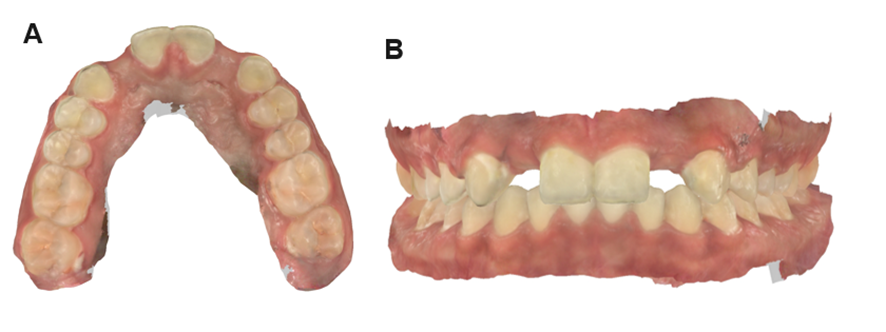

O planejamento envolveu o escaneamento oral das arcadas e registro de mordida por meio do iTero™.

A projeção tridimensional do trabalho foi realizado com o CAD/CAM®, com o planejamento do implante e da prótese. Isso garante a previsibilidade da etapa cirúrgica e protética, bem como as posições ideais e angulações favoráveis.